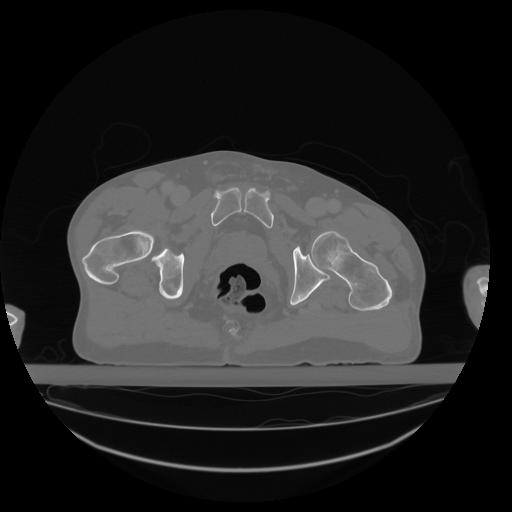

34 CUERPO,CE,Vol,1.0,CUERPO,,